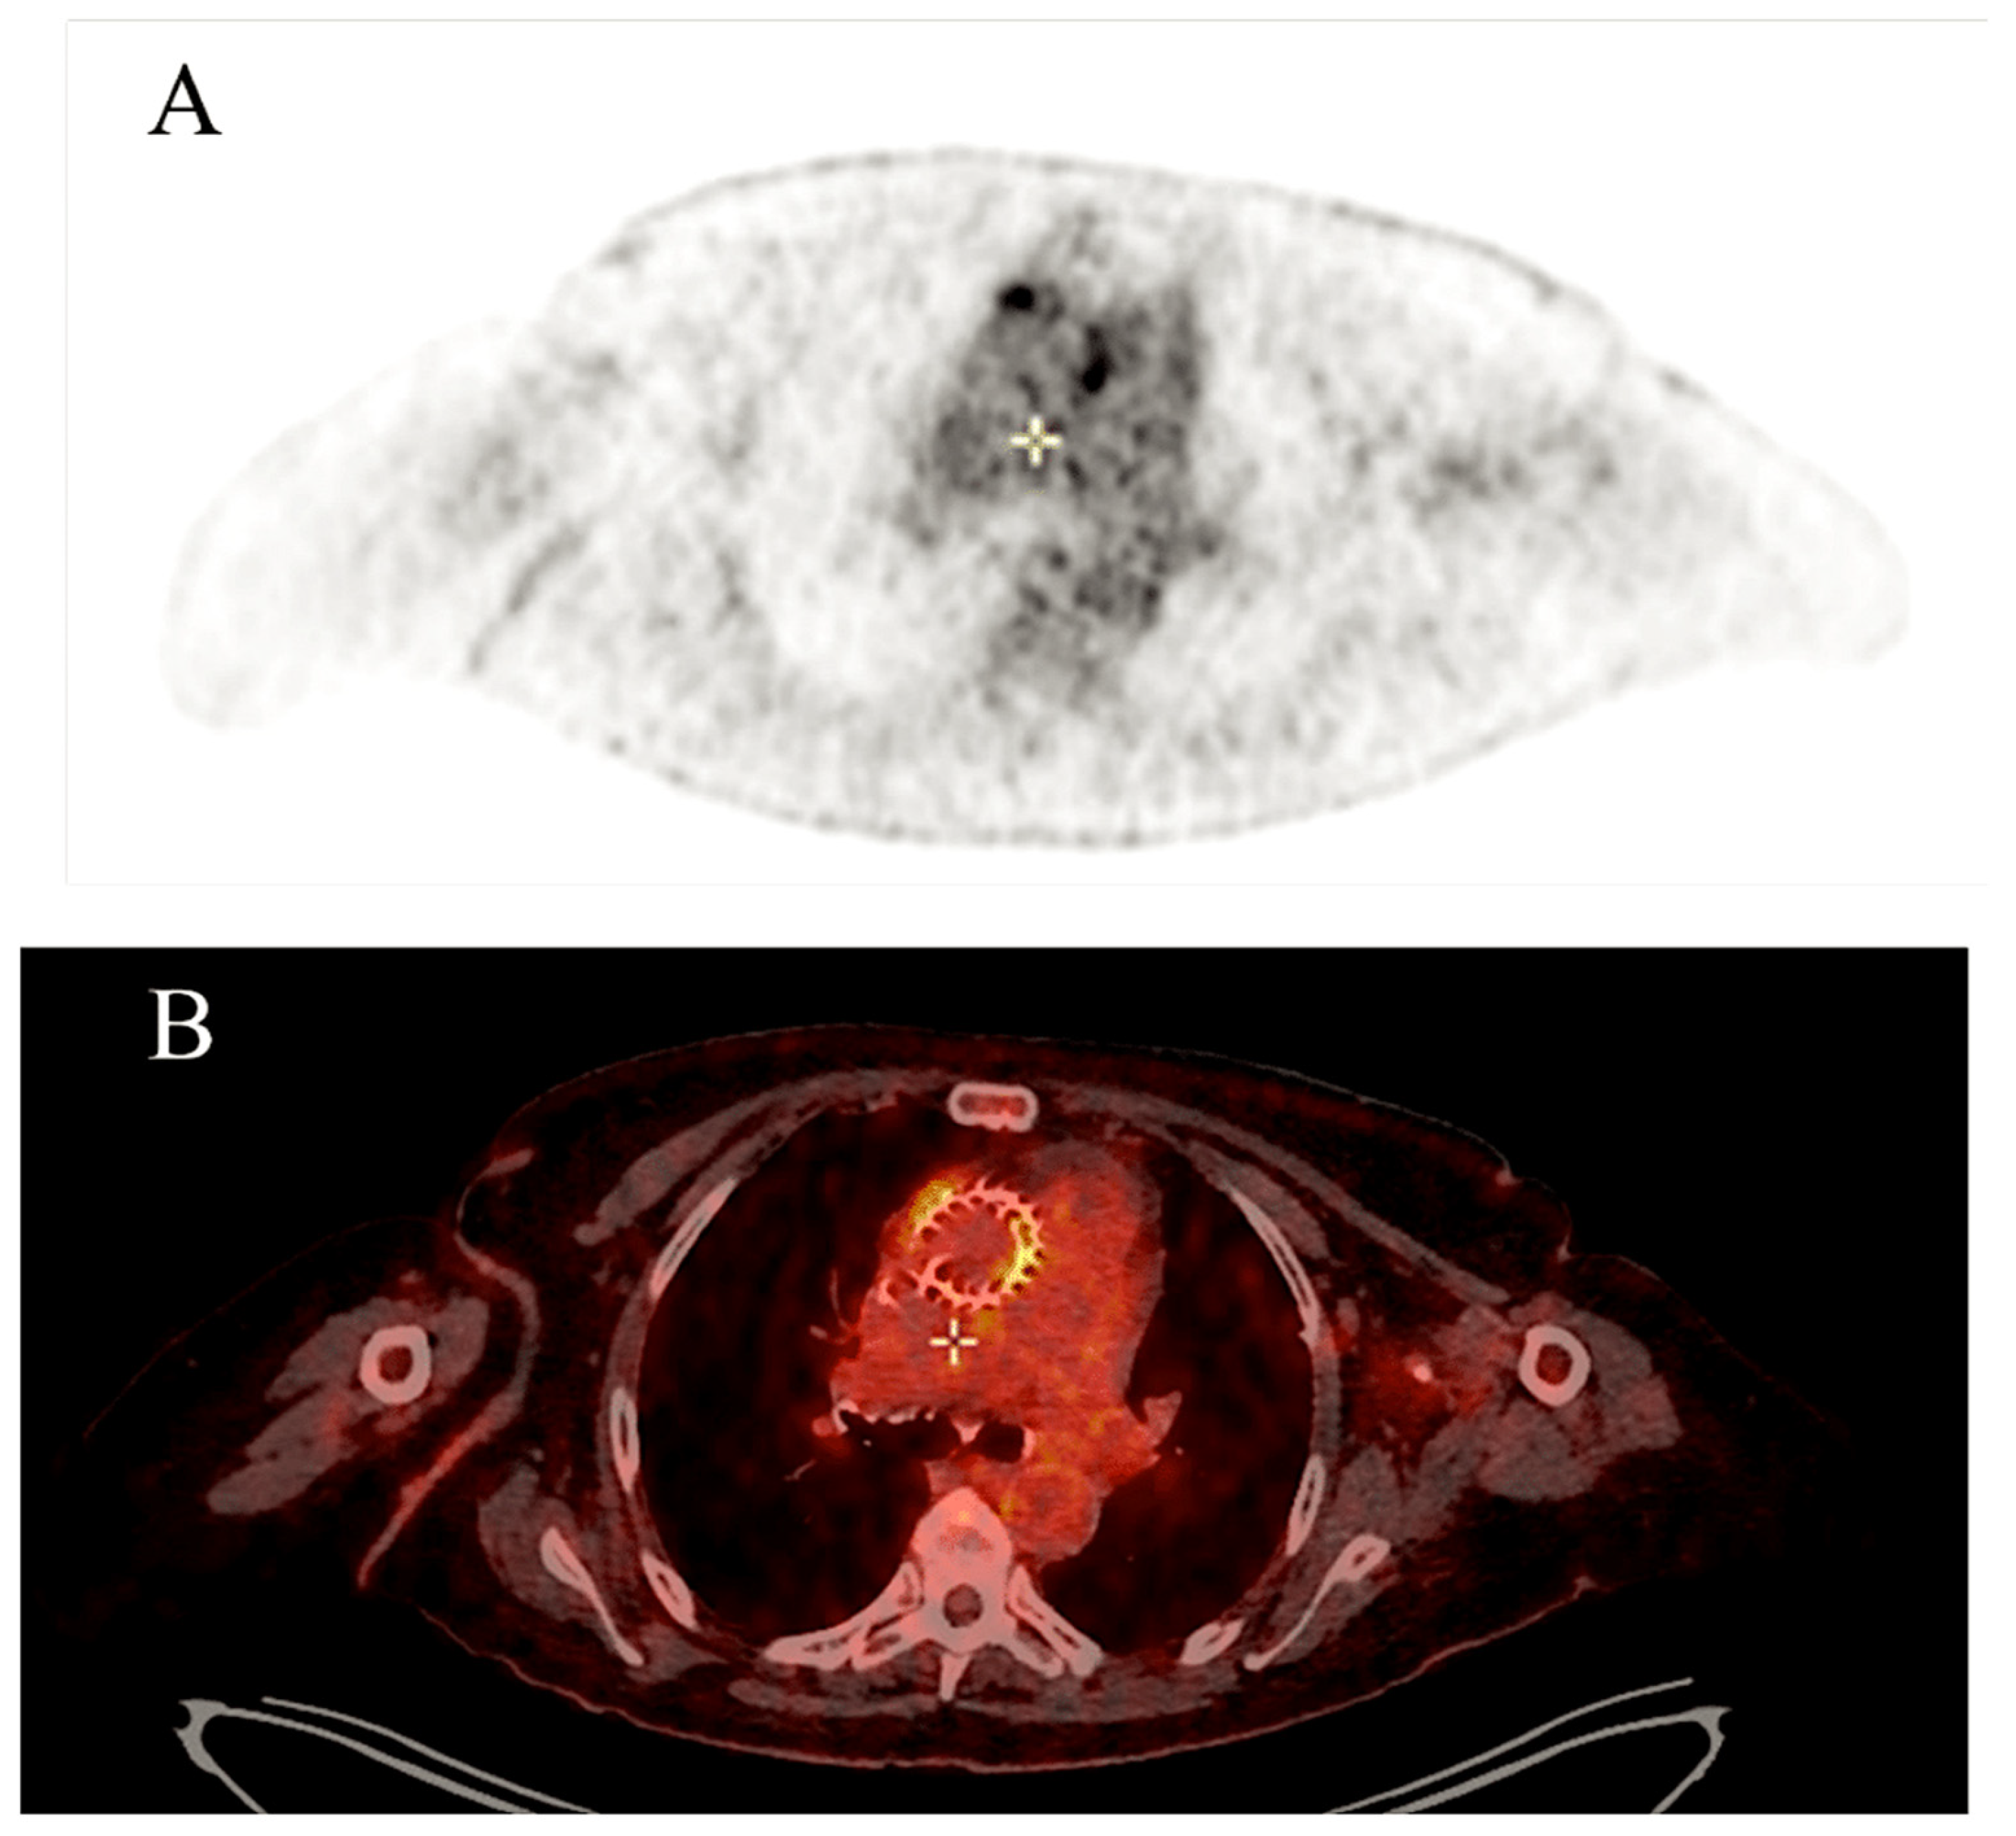

4.4. Impact of Imaging Techniques

- Saby, L.; Laas, O.; Habib, G.; Cammilleri, S.; Mancini, J.; Tessonnier, L.; Casalta, J.P.; Gouriet, F.; Riberi, A.; Avierinos, J.F.; et al. Positron emission tomography/computed tomography for diagnosis of prosthetic valve endocarditis: Increased valvular 18F-fluorodeoxyglucose uptake as a novel major criterion. J. Am. Coll. Cardiol. 2013, 61, 2374–2382. [Google Scholar] [CrossRef] [PubMed]

- Pizzi, M.N.; Roque, A.; Fernández-Hidalgo, N.; Cuéllar-Calabria, H.; Ferreira-González, I.; Gonzàlez-Alujas, M.T.; Oristrell, G.; Gracia-Sánchez, L.; González, J.J.; Rodríguez-Palomares, J.; et al. Improving the diagnosis of infective endocarditis in prosthetic valves and intracardiac devices with 18F-fluorodeoxyglucose positron emission tomography/computed tomography: Initial results at an infective endocarditis referral center. Circulation 2015, 132, 1113–1126. [Google Scholar] [CrossRef] [PubMed]

- Granados, U.; Fuster, D.; Pericas, J.M.; Llopis, J.L.; Ninot, S.; Quintana, E.; Almela, M.; Paré, C.; Tolosana, J.M.; Falces, C.; et al. Diagnostic accuracy of 18F-FDG PET/CT in infective endocarditis and implantable cardiac electronic device infection: A cross-sectional study. J. Nucl. Med. 2016, 57, 1726–1732. [Google Scholar] [CrossRef] [PubMed]

- Wahadat, A.R.; Tanis, W.; Swart, L.E.; Scholtens, A.; Krestin, G.P.; van Mieghem, N.M.; Schurink, C.A.; van der Spoel, T.I.; van den Brink, F.S.; Vossenberg, T.; et al. Added value of 18F-FDG-PET/CT and cardiac CTA in suspected transcatheter aortic valve endocarditis. J. Nucl. Cardiol. 2021, 28, 2072–2082. [Google Scholar] [CrossRef]